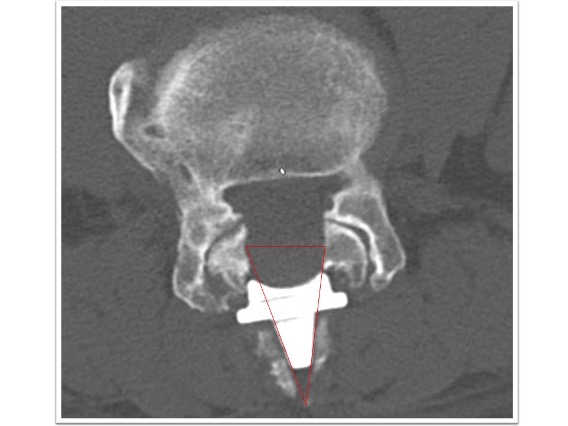

頚椎症性脊髄症

上肢の運動障害、歩行障害の患者様に対して頚椎椎弓形成術を実施。術後MRI画像で頚髄の圧迫が解除され頚髄前後にスペースが生まれています(図赤丸)。また、CT画像では術前後の比較で脊柱管の前後幅が約1.5倍以上に拡大していることが確認できます(図青矢印)。術後は歩行安定し、上肢運動も改善しています。